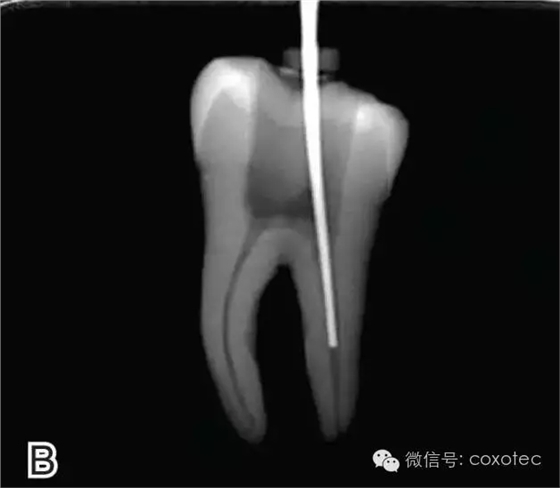

以下本文摘自網(wǎng)絡,對連續(xù)波熱牙膠充填技術的操作通俗易懂,以供臨床醫(yī)生學習和參考。感謝原作者辛苦制作和分享。 前言:連續(xù)波熱牙膠充填技術是目前臨床上應用最廣泛的一種熱牙膠充填技術,其將熱牙膠垂直加壓充填技術的多步加熱和加壓改良為加熱加壓同時完成,簡化了充填步驟,提高了充填效率。本文將介紹其具體操作步驟。 操作步驟 根據(jù)預備后根管的粗細選擇相應型號的攜熱器工作尖。 要求工作尖能自由到達距根尖4~5 mm(有學者提出3~4 mm)的位置并能輕微接觸根管壁,用橡皮片做好標記(圖1) 圖1 選擇攜熱器工作尖,A.試攜熱器尖 B.工作尖在根內的位置

選擇的小號垂直加壓器應能自由到達距根尖4~5 mm(有學者提出3~4 Mm)的位置并能輕微接觸根管壁;中號垂直加壓器應能自由到達距根尖7~8 mm的位置并能輕微接觸根管壁;大號垂直加壓器應能自由到達距根尖10~11 mm的位置并能輕微接觸根管壁。用橡皮片做好標記(圖2)。

圖2 選擇垂直加壓器,A.試垂直加壓器 B.垂直加壓器在根內的位置 選擇非標準牙膠尖(如0.04、0.06 錐度牙膠尖)作為主尖,型號一般與根管預備最大號的器械型號一致,能到達距根尖0.5~1 mm 處,主尖尖段與根管壁緊密接觸。拍試尖X 線片進行確認(圖3)。